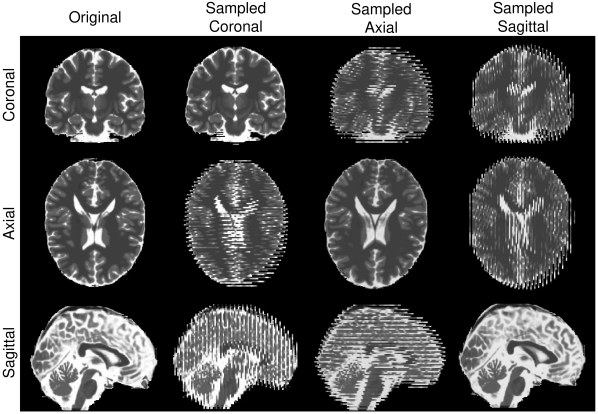

Reconstruction of Adult Brain MRI: Experiments on adult brain MR data using the Brainweb database [34] included introducing synthetic non-rigid motion artifacts as described in Sec. IV. Example slices of standard planes of original and corrupted data are depicted in Fig. 9. Comparative experimental results of SVR and PVR reconstruction methods are shown in Fig. 10 for PSNR, SSIM and CC. For all metrics, PVR shows an improved performance over SVR, particularly in presence of deformations with higher skewing angles. Further, we observe that superpixel-based PVR achieves similar performance as PVR using arbitrary square patches, while requiring a lower amount of input patches.